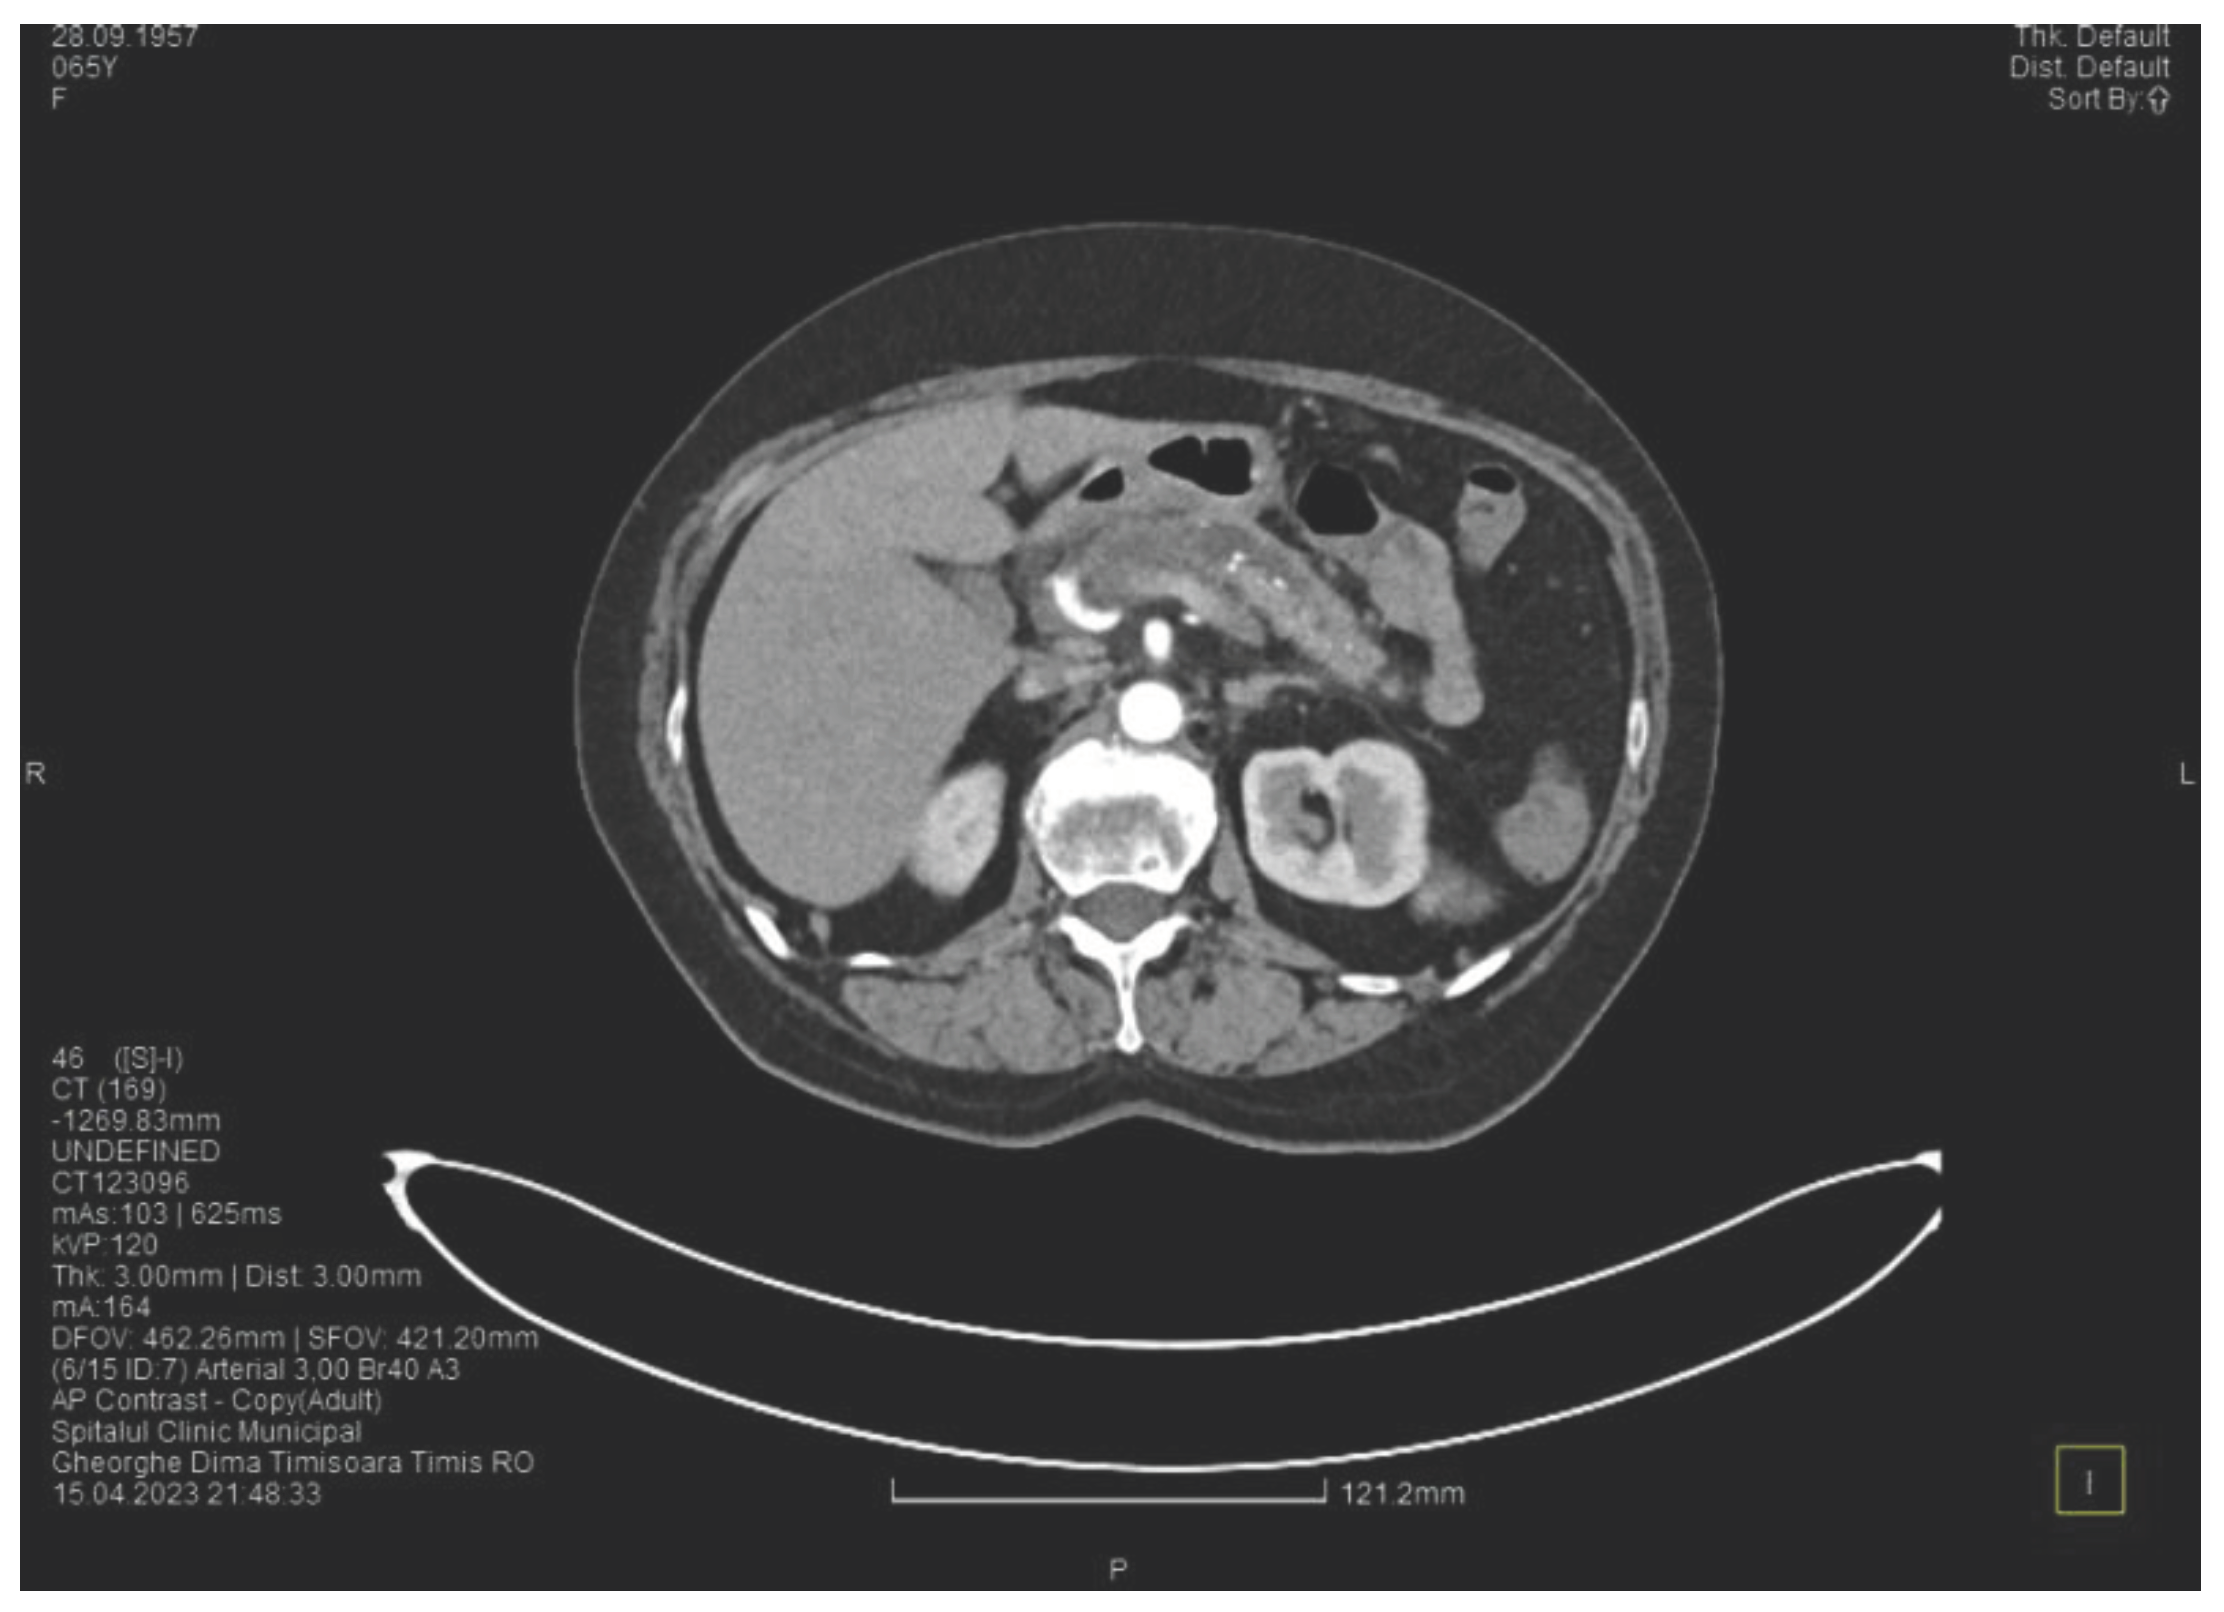

Laboratory tests show a serum lipase of more than 10 times above the upper normal range. The contrast enhanced computed tomography (CT) shows multiple calcifications in the pancreatic tissue, dilatation of the main pancreatic duct of approximately 12.5 mm (Figure 1), a non-iodophilic intraparenchymal cyst in the head of the pancreas with a size of 23/25 mm that associates acute inflammation (Figure 2) and a densification of the peripancreatic fat, more intense at the head of the pancreas, as well as enlarged pericephalic and periaortocaval lymph nodes. There were no changes in the liver and the gallbladder, only a mild ectasia of the intrahepatic bile ducts, with no dilatation of the common bile duct. Other changes include multiple atheromas of the abdominal aorta. The symptoms, the lab results and the finding at CT scan led to the diagnosis of acute pancreatitis.

Figure 1. The initial CT scan shows the dilated Wirsung duct and calcifications in the pancreatic tissue.